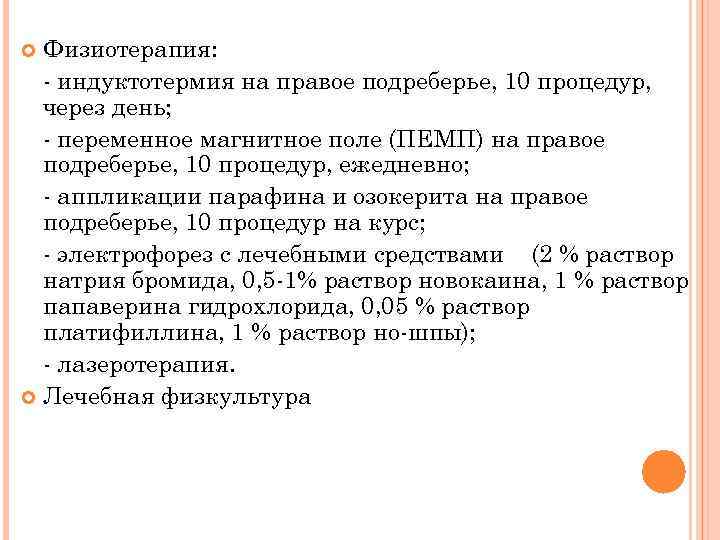

Физиотерапия: - индуктотермия на правое подреберье, 10 процедур, через день; - переменное магнитное поле (ПЕМП) на правое подреберье, 10 процедур, ежедневно; - аппликации парафина и озокерита на правое подреберье, 10 процедур на курс; - электрофорез с лечебными средствами (2 % раствор натрия бромида, 0, 5 -1% раствор новокаина, 1 % раствор папаверина гидрохлорида, 0, 05 % раствор платифиллина, 1 % раствор но-шпы); - лазеротерапия. Лечебная физкультура